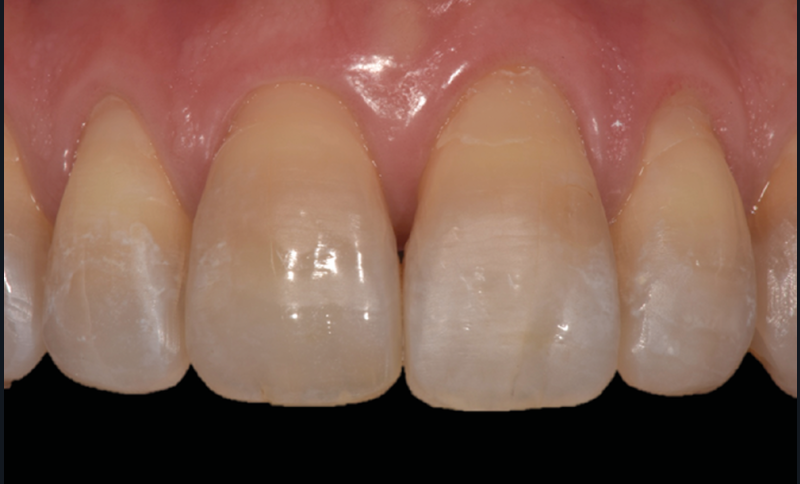

Le Pr Olivier Sorel insistera sur l’importance du respect des formes et des proportions anatomiques, pour éviter de voir apparaître, notamment chez les adultes, de très inesthétiques triangles noirs lors de la phase d’alignement (fig. 6a-b). Il présentera sa démarche diagnostique (évaluation de la forme des dents et de la dysharmonie dento-dentaire, fig. 7a-c) et l’intégration de la réduction amélaire proximale au plan de traitement, afin de s’assurer, en fin de traitement, la présence de papilles gingivales et donc d’un sourire harmonieux (fig. 8a-d).

Les Drs Marie Clément et Clara Marcoux aborderont ensuite les différents apports de la dentisterie esthétique aux traitements orthodontiques. Les problèmes de dyschromies isolées ou généralisées, congénitales ou acquises seront développés ainsi que les anomalies de proportions dentaires (dents riziformes…), le maquillage (transformation d’une canine en incisive latérale…) et le remplacement des dents antérieures. Les auteurs présenteront l’intérêt du Digital Smile Design dans le diagnostic et la communication et l’arsenal thérapeutique à notre disposition pour améliorer la satisfaction de nos patients (éclaircissement, traitement des taches de l’émail, composites stratifiés, fig. 9a-d).